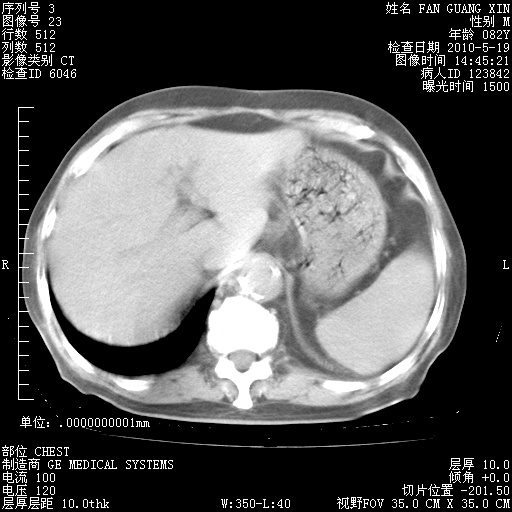

还需要哪些辅助检查?我们医院排除真菌感染没有任何检验方法,胸片好像能够排除肺部真菌感染。

补充:ENA化验全部阴性。免疫五项(IgG、IgA、IgM、C3、C4)只有C4略高。

CD3+ T细胞/淋巴细胞 46% (参考值50.00~84.00%)

CD3+CD4+ T细胞/淋巴细胞 21% (参考值27.00~51.00%)

CD3+CD8+ T细胞/淋巴细胞 25% (参考值15.00~44.00%)

CD3+CD4+ T细胞/CD3+CD8+ T细胞 0.84 (参考值0.71~2.78)

T细胞亚群是治疗5天采血。